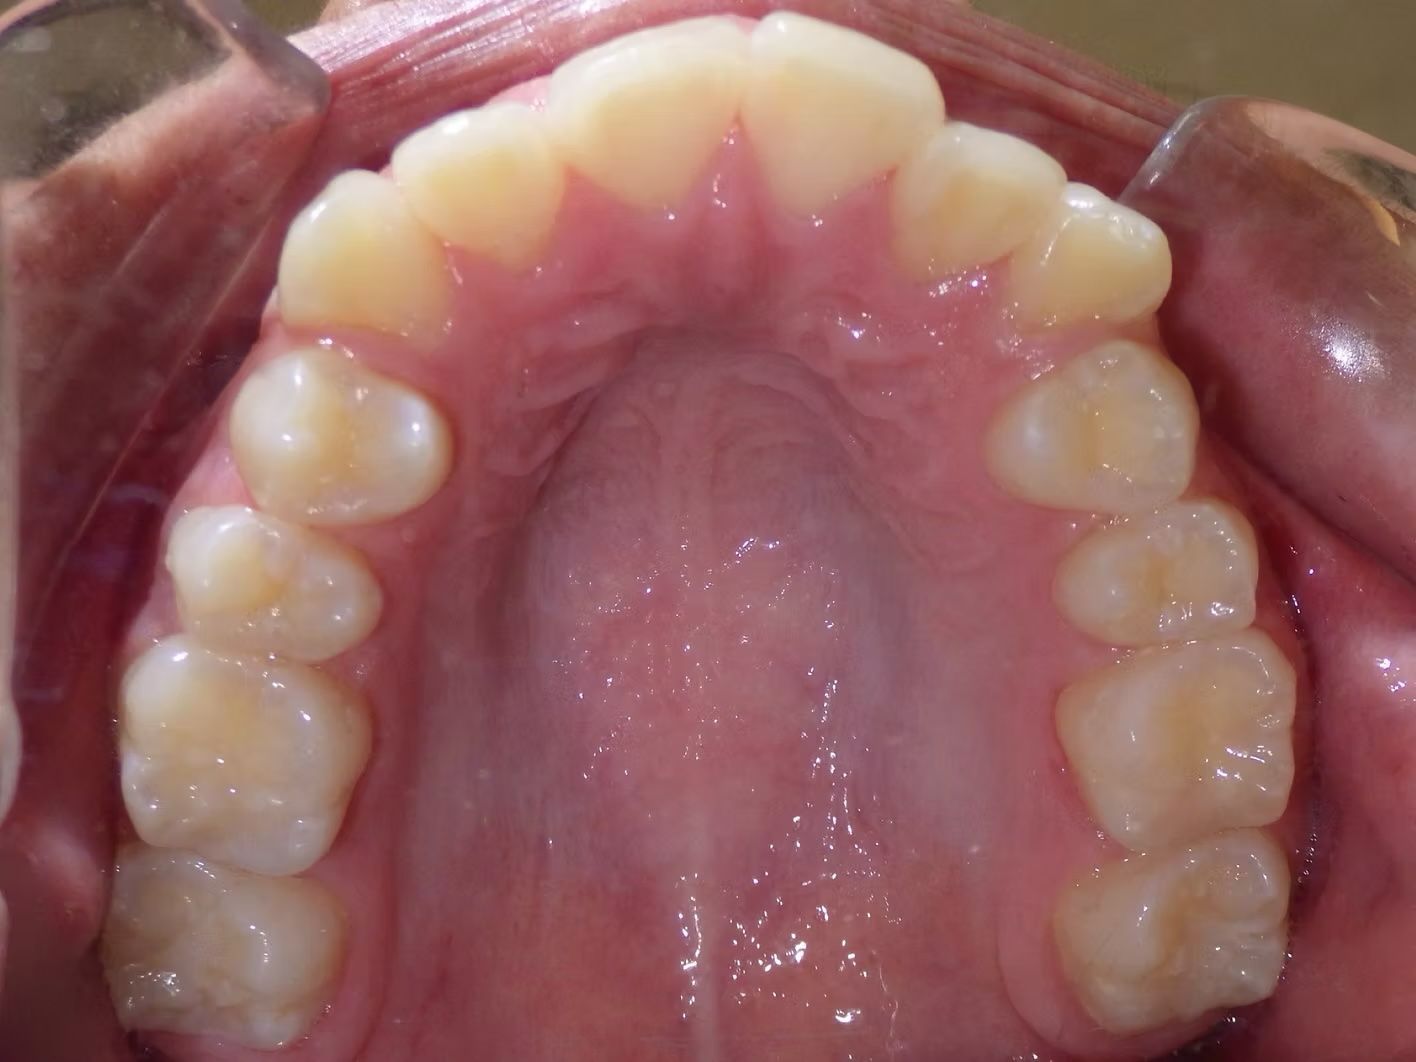

BRIANNA

Brianna's lower left 1st premolar was completely in a brodie bite (outside the normal arch) and her top and bottom teeth were very crowded. Dr. Freedman corrected her bite and crowding without removing any teeth.